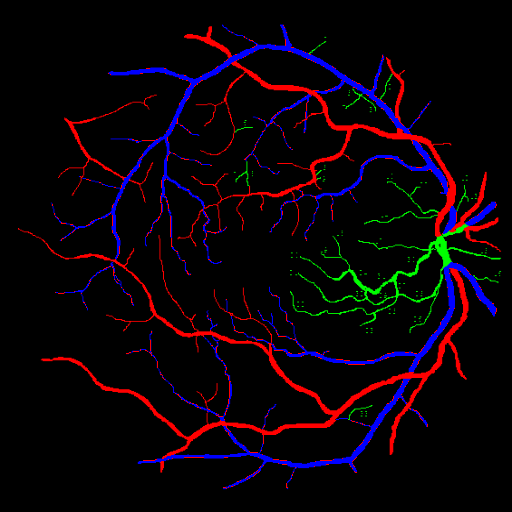

For better explainability of the result, Tables 4 and 5 and the activation map of the final layer can be observed. In Fig. 7, the first image corresponds to the ground image, the first column corresponds to the activation map of the artery and vein channel of the Attention-UNet Model trained for Separate Artery-Vein segmentation, and the second column corresponds to the activation map of artery and vein channel of the Attention-WNet Model trained for binary segmentation model. It can be observed that the latter model is more confident about the vessel’s nature than the former. The fundus image, ground truth, and the corresponding sample outputs provided by Attention UNet and Attention-WNET are shown in Figure 6. It can be observed that some of the vein pixels have been marked as artery pixels by Attention UNet. In this case, Attention WNet predicts better than Attention UNet. It shows the proposed approach’s capability to distinguish between arteries and veins. It is also observed that the model is comparatively more confident about artery pixels than veins, further confirming the complexity involved in identifying veins even though the latter performs comparatively better.

Refer to caption

(a)

(b)

(c)

(d)

Figure 6: Comparing Attention UNet and Attention WNet output for a given fundus image